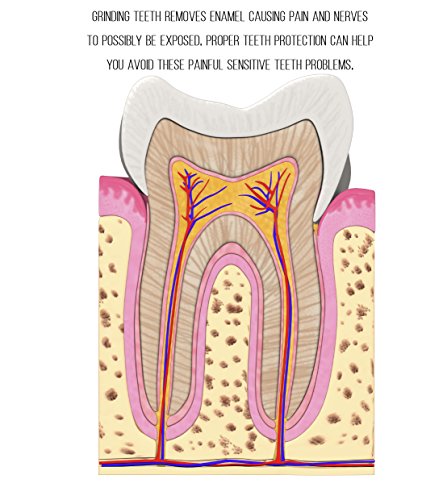

Do You Suffer From Any of These?: - Bruxism - Teeth Grinding - TMJ - Jaw Joint Pain - Headaches Are you tired of waking up in the night with interruptive and often painful sleep issues? Right now is the moment that you can take control of your sleep, and your life, and choose a better life NOW Incredible Sleep Just One Click Away Stop painful grinding, clenching, bruxism, TMJ, and so many other sleep issues right in their tracks! Trouble sleeping because you sleep with your mouth open? This is the solution. Our Proprietary Grind Free Bruxism Night Guard can Solve Your Sleeping Issues Tonight! If you want the best sleep aid on the market, this is the product for you. A great night's sleep is in your grasp will you take advantage of it? This could be the most important decision of your life, without proper rest you can NEVER function at 100% For a Limited Time Only, You can try the Grindfree Sleep Aid RISK FREE. We guarantee that you will get the best sleep you have ever gotten or you will be awarded a FULL REFUND. Just Return Your Product Within the First 30 Days, No Questions Asked! "Amazingly Simple Device Helps Thousands of People Get Restful Sleep"